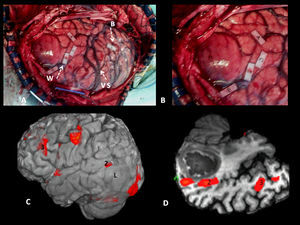

Las áreas corticales implicadas en el lenguaje (fig. 1) correlacionadas con la estimulación cortical (tabla 2) fueron:

Frontales: circunvolución frontal inferior (área de Broca), pars triangular y opercular; córtex facial motor (margen más inferior de la circunvolución frontal ascendente); córtex premotor (anterior al córtex facial motor); área motora suplementaria (medial a la parte más craneal del surco precentral).

Temporoparietales: córtex temporal posterior izquierdo: tercio posterior de las circunvoluciones temporales superior y media; lóbulo parietal inferior izquierdo: circunvoluciones angular y supramarginal.

Occipitotemporal basal: circunvoluciones temporal inferior y fusiforme. Son áreas relacionadas con el reconocimiento visual, especializadas en la identificación de la forma de las palabras o de los objetos, como el giro fusiforme izquierdo («visual word form area» y «visual object-form area»).

RM funcional volumétrica. A) Áreas corticales frontales, B) temporoparietales y C) occipitotemporal basal implicadas en el lenguaje. 1: Área de Broca; 2: Córtex premotor; 3: Córtex facial motor; 4: Área motora suplementaria; 5: Área de Wenicke; 6: Área visual de la forma de la palabra «Visual word form area». **Áreas de asociación auditiva.

En el caso de los fascículos subcorticales «funcionales» la concordancia fue del 100%. Los haces correlacionados fueron (tabla 3) (fig. 2):

Fascículo arcuato: parte medial del fascículo longitudinal superior, conectando el córtex lateral frontal y parietotemporal.

Fascículo o haz frontoparietal: parte lateral del fascículo longitudinal superior, conectando el área de Broca con el lóbulo parietal inferior.

Fascículo frontooccipital inferior: conecta áreas prefrontales y occipito-temporoparietales mediales. En su tercio anterior se sitúa craneal al techo del asta temporal y a las radiaciones ópticas. En su segmento temporooccipital posterior es lateral al asta occipital ventricular, entrando a formar parte del stratum sagital. Termina en el córtex medial temporoccipital.

Fascículo longitudinal inferior: en su trayecto temporooccipital izquierdo interviene en la identificación de la forma de los objetos o «visual object-form area».

Fascículo subcalloso: rodea el cuerno frontal ventricular y conecta el área motora suplementaria con el cíngulo y el núcleo caudado.

Tractografía 3D. Fascículos subcorticales funcionales implicados en el lenguaje. FA: fascículo arcuato (flecha corta continua); FFOI: fascículo frontooccipital inferior (flecha larga discontinua); FLI: fascículo longitudinal inferior (flecha larga continua); FP: haz frontoparietal; FU: fascículo uncinado (flecha corta discontinua).

Otro haz identificado fue el fascículo uncinado (fig. 2) que conecta el córtex frontotemporal anterior, no implicado aparentemente en el lenguaje. Sirve como punto de referencia en la localización del fascículo frontooccipital inferior y es punto de partida del asa de Meyer y de las radiaciones ópticas (fig. 3) (trayecto temporooccipital posterior formando parte del stratum sagital, en situación lateral al asta occipital, con curvadura medial hacia la cisura calcarina).

Correlación cortical entre la RM funcional y el mapeo eléctrico quirúrgico en el mismo paciente de la figura 4. A) Mapeo intraoperatorio. Paciente en decúbito lateral derecho. 4: Córtex facial motor; 3: córtex premotor; 5, 6: área de Broca; 8: eye field frontales. Correlación con la RM funcional (B, C y D): áreas de activación coincidentes con el mapeo cortical. *Área motora suplementaria. A: anterior; P: posterior.

Correlación subcortical entre la imagen de tensor de difusión (ITD) y el mapeo eléctrico quirúrgico en el mismo paciente de las figuras 4 y 5. A) Mapeo subcortical intraoperatorio. Paciente en decúbito lateral derecho. 41: Fascículo frontooccipital inferior (FFOI). B) Correlación cortical con la RM funcional: 3: córtex premotor; 5: área de Broca; 8: eye field frontales. Reconstrucciones sagitales 3D-ITD del FFOI. C y D) El margen posterior del FFOI (41) (flecha) limita la resección posterior del tumor.